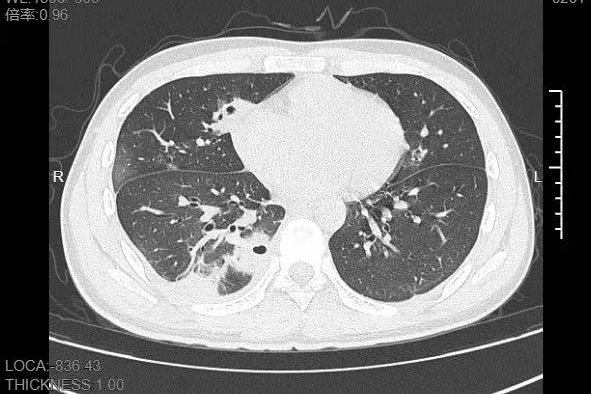

熬到第三天,小林已经烧到39℃,他赶紧来到宁波大学附属第一医院就诊。接诊的呼吸与危重症医学科主任医师丁群力一看他的症状,立刻安排了CT检查。结果显示:小林的肺里有十几个空洞,部分肺组织已经坏死,这是典型的血源性肺脓肿。